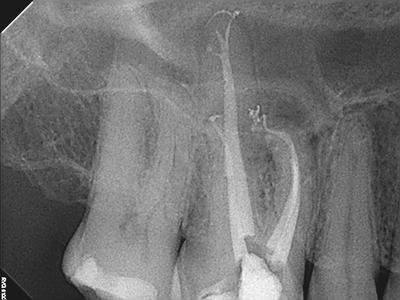

Radiographic Examination:

Tooth # 3 exhibits severe pulpal calcification, periapical radiolucencies associated with all 3 roots and severe dilaceration of the mesiobuccal root.

Conventional non-surgical root canal therapy

Restorative: Cotton and Cavit. Patient to return to GP for full coverage restoration